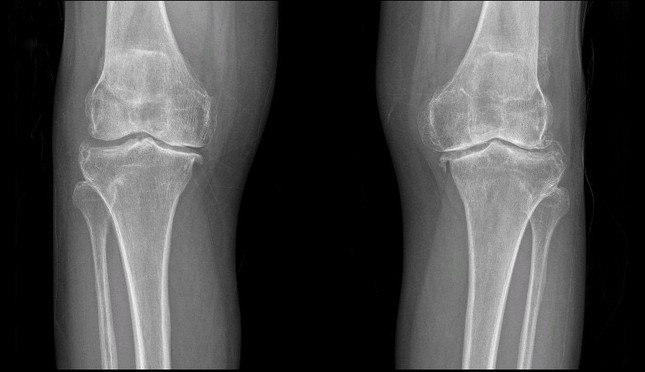

Khám lâm sàng và chẩn đoán hình ảnh: Thực hiện X-quang, MRI hoặc CT để xác định mức độ tổn thương khớp và lựa chọn loại khớp nhân tạo phù hợp.

Chụp X-Quang đánh giá tình trạng khớp trước phẫu thuật